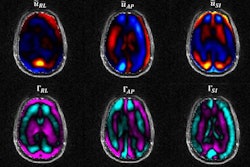

Several DOE national laboratories and UCSF are collaborating on the Transforming Research and Clinical Knowledge in Traumatic Brain Injury (TRACK-TBI) consortium. Using data deidentified from 3,000 TBI patients from TRACK-TBI, the Lawrence Livermore National Laboratory (LLNL), Lawrence Berkeley National Laboratory (LBNL), and Argonne National Laboratory (ANL) will employ AI techniques and DOE supercomputers to analyze CT and MRI studies, proteomic and genomic biomarkers, and clinical outcomes. These systems will be integrated into the DOE's research in science and energy, as well as national security programs.

The project began in March and is still in its initial stages. Teams at the DOE and USCF are continuing to work on the connectome -- a model of the structural connectivity of the human brain. Meanwhile, scientists at the LBNL and ANL are focusing on data analytics, including genetic information and CT scans of TBI patients, according to the LLNL.